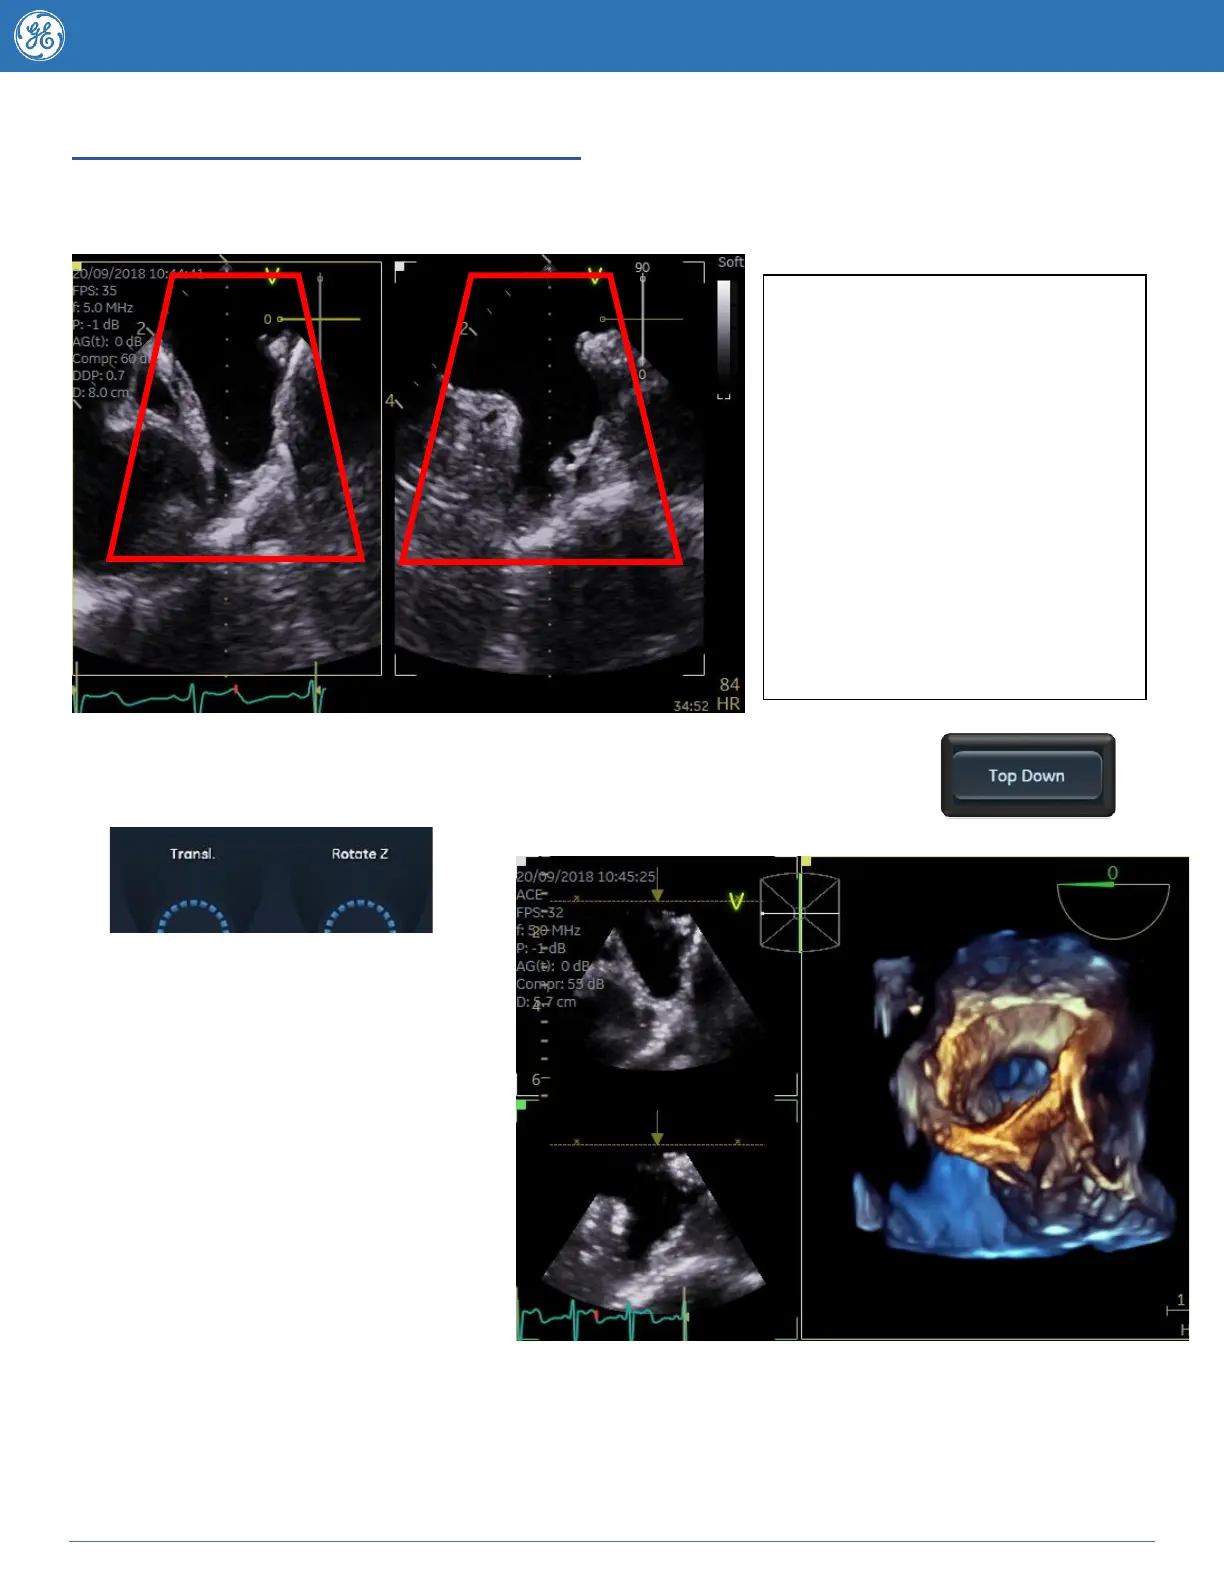

Using the 4D zoom TOP DOWN button

4D zoom Top Down is helpful for any structure you wish to see from the Top down, this makes it

especially helpful for 4D left atrial appendage and interatrial septum acquisition.

When you are ready to view your 4D image press the Top Down button on the

touchscreen and you will be taken through to the 4D rendered view.

The Rotate Z knob can be used the

adjust the angle of the 4D dataset if it’s

a couple of degrees off (represented by

yellow arrow).

The “Yellow” arrow on the 2D reference

planes represents the viewing

direction.

The brown Translate line (visible on

the 2D images) can be moved using

the translate knob at the bottom of the

touchscreen to optimize the image

move it closer to the region of interest

you can also use 2 Click Crop to

crop the image down in a parallel fashion.

Remember a darker 2d image may produce a nicer 4D image if it’s difficult to see the structures due

to blurring try turning down the large 2D gain knob.